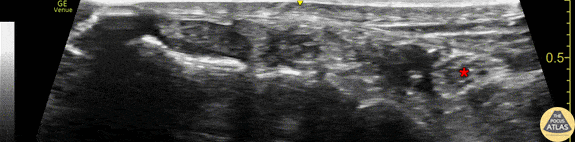

Anatomy of the tibial nerve as it passes posterior of the medial malleolus. The image was obtained using the linear transducer in a transverse orientation just posterior to the medial malleolus. The nerve (*) is seen posterior to (right of) the pulsating posterior tibial artery. Also seen is the hyperechoic malleolar cortex of the distal tibia at the bottom of the image, as well as the tendons of tibialis posterior and flexor digitorum longus anterior to (left of) the artery and nerve. Drs. Sam Paskin-Flerlage, PGY4 and Michael Heffler, PGY3 Denver Health Residency in Emergency Medicine